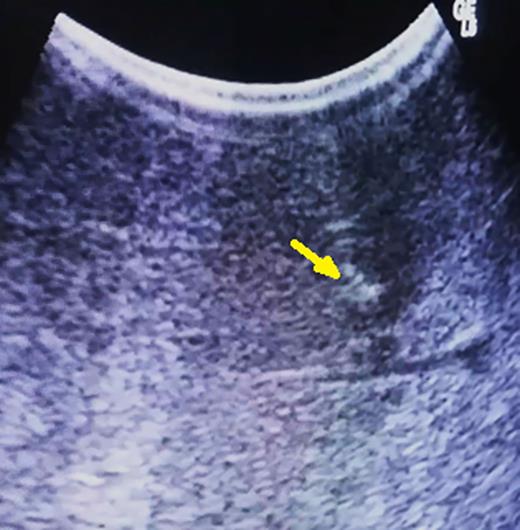

If the tumor is not retrieved with the specimen, despite the bleeding caused by parenchymal transection, further inspection of the manipulated hepatic bed will disclose the presence of methylene blue, and under direct visualization of the area of the tumor, a second specimen is retrieved containing the lesion (Fig. 4).

(A) Methylene blue-injected area containing the tumor within the parenchyma and (B) two specimens: the smaller one, that was displaced deeper within the parenchyma, containing the tumor.